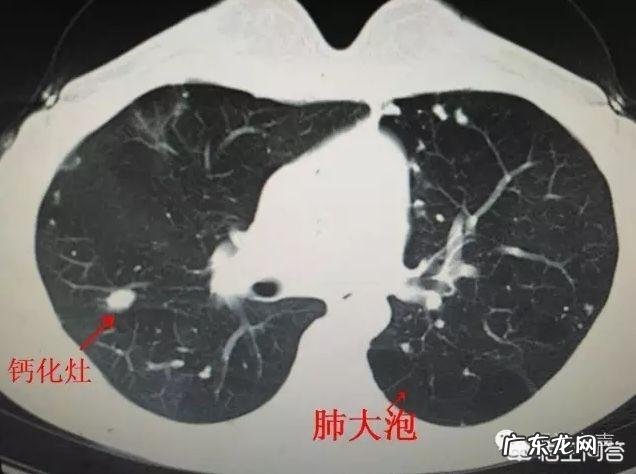

文章插图